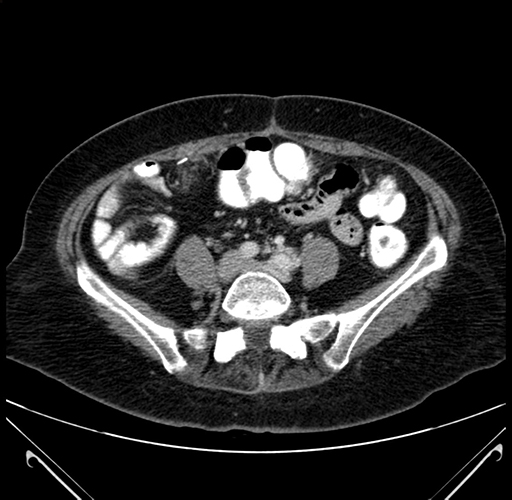

Axial Venous